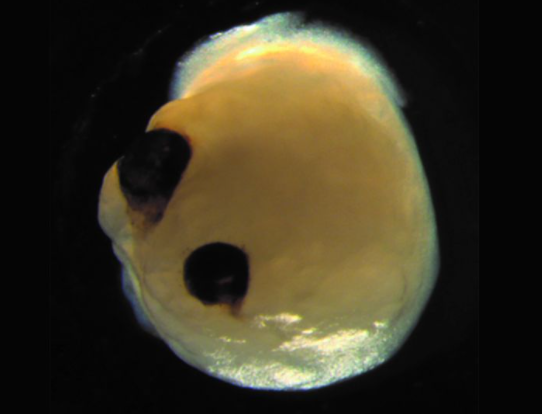

1. Выращивание миниатюрного человеческого мозга собственными глазами.

В августе 2021 года, группа ученых сообщила новость, которая в равной степени восхищала и ужасала, объявив, что им удалось успешно вырастить в лаборатории крошечный человеческий мозг с собственной парой глаз. Они создали мини-мозг в стиле Кроненберга (Канадский режиссер, сценарист, актер, оператор, монтажер, продюсер), называемый органоидом, путем преобразования стволовых клеток в нейронную ткань, а затем стимулировали клетки химическими сигналами для формирования крошечных рудиментарных "зрительных чашек", наполненных светочувствительными клетками.

К счастью для нашего коллективного здравомыслия и для самих мини-мозгов, крошечные органоиды не обладают достаточной нейронной плотностью, чтобы быть сознательными - так что в ближайшее время они не будут спрашивать себя, как они пробудились в качестве потерянной пары глаз, скользящих по чашке Петри. Однако они являются невероятно полезными конструкциями для изучения развития мозга и потенциального создания лекарств для лечения заболеваний сетчатки, вызывающих слепоту.